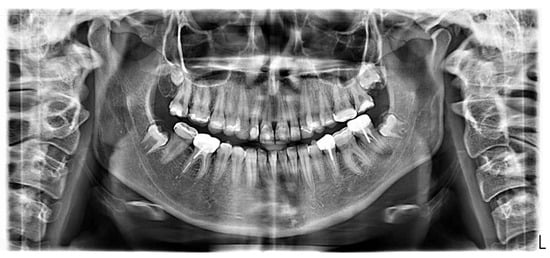

2.3. Radiographic Examinations

2.7. Management of the Posterior Mandibular Teeth (Second Session)

2.8. Management of the Maxillary Molars (Third and Fourth Sessions)